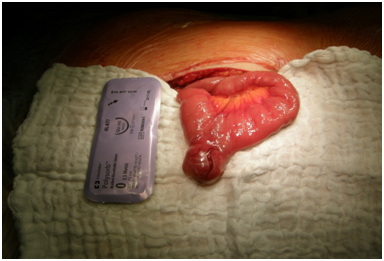

A 40-year old woman (M.B., history number: KG-43875/14) was admitted to the Department of General and Colorectal Surgery, University of Medical Sciences in Poznań on August 26,2014 because of massive lower GI bleeding. On physical examination patient was pale with signs of severe hypovolemia, BP 105/50, HR 115-120/min, abdomen was soft, painless, without rebound tenderness, without distension, peristals is audible, fresh blood was detected on rectal examination. Laboratory tests: hemoglobin-4,4mmol/l, hematocrite 21%, red blood cell count -2,4x106/µl, white blood cell count - 13,6x103/µl, electrolytes, blood urea, nitrogen, creatinine, glucose, amylase, bilirubin, aminotransferase within the recommended range. Coagulation parameters within normal limits. After admission intensive initial fluid resuscitation was started, blood and fresh frozen plasma transfusions were given and emergency endoscopy was performed. Gastro copy ruled out duodenal haemorrhage. Colonoscopy revealed fresh blood in the entire colon and the active outflow of blood from terminal ileum but the bleeding site was not identified. Since the patient started to deteriorate with obvious signs of hypovolemic shock despite blood trasfusions and fluid resuscitation, the decision for urgent operation was made, suspecting small bowel haemorrhage. The abdominal cavity was opened via ventral midline incision. There were no signs of inflammatory fluid or blood in the peritoneal cavity. A thorough exploration of small intestine revealed the tumor of the jejunum about 70cm from the ligament of Treitz causing massive bleeding to the lumen of the bowels (Figure 1). Radical resection of the tumor and adjacent jejunum with mesentery was performed followed by side -to-side anastomosis using the linear cutterstapler. Postoperative period was uneventful and the patient was eventually discharged home in a good condition on the 7th day after the operation. Postoperative initial histopathology examination showed fusocellular tumor 17x25x20mm with 3mitoses/50 HPF. Additional immunohistochemistry examination confirmed the diagnosis of GIST with characteristic immunophenotype: CD 117+, DOG1+, CD34+, SMA-, S100-, CKAE1/3-, Ki 67<2%.

Figure 1 Intraoperative image at laparotomy demonstrating rectal injury gastrointestinal stromal tumor of the jejunum.